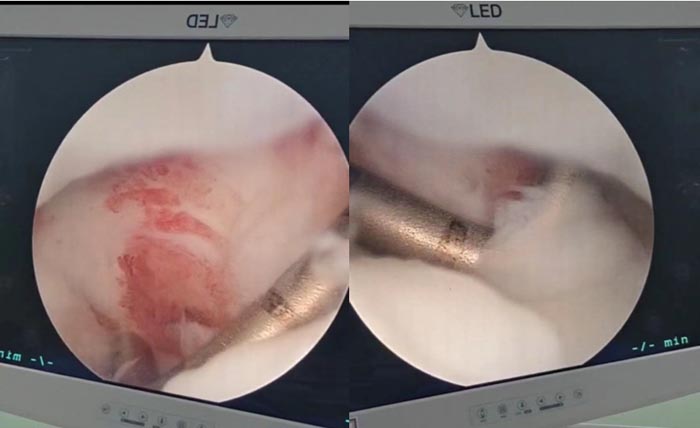

近日,患者顾某骑车摔倒左手撑地后出现腕部疼痛,在正规治疗后一段时间,疼痛仍无好转,腕关节依旧不能灵活运动,他辗转至手足外科蔡卫明主任门诊,蔡主任根据其病史、查体,同时结合MRI结果仔细评估后,考虑顾某是三角纤维软骨复合体 (triangular fibrocartilage complex,TFCC) 损伤,建议其入院进一步治疗。顾某一听,小小的毛病竟然要动手术,顿时大惊失色,怕术后给自己的生活和工作带来诸多不便。蔡主任洞察到他的顾虑,随即解释了该手术属于微创手术,切口小、创伤小、恢复快、皮肤瘤痕也极小,不影响到他今后的方方面面。顾某在仔细听完蔡主任的介绍后,思考片刻欣然接收手术治疗,随即办理入院手续。顾某在术后三天即康复出院,他对术后效果也相当满意。

术中情况:

以前对这种腕关节疼痛的病人治疗困难,主要是因为对这种疾病认识不足,病人只能长期忍受腕关节的疼痛。且腕关节间隙较小,开放手术操作困难、创伤大,故治疗效果不佳。对此,我院手足外科2021在泰州地区率先引入腕关节镜,进行腕关节镜下微创检查手术,取得了极好的治疗效果。

蔡卫明主任介绍,随着内镜的技术的日益成熟,膝关节镜及肩关节镜的检查治疗已被人们广泛熟知。但由于腕关节间隙小、解剖复杂,导致镜下手术长期难以突破,只有部分大型三甲医院可以开展。随着2.7mm腕关节镜的引入,使镜下的检查和手术成为可能。腕关节镜治疗腕关节病变具有创伤小、恢复快、可同时处理关节内合并病变、无需辅助开放切口等优点。